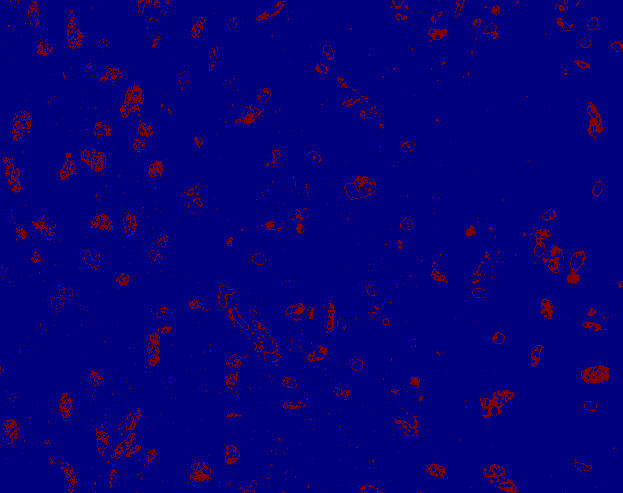

Technical Details

Pipeline

Thresholding

K-means clustering

Parameters:

- number of color clusters

- number of most most intensive clusters to be classified as nuclei

Models

- k-means(3,1)

- k-means(4,2)

- k-means(6,3)

input

color clusters

1

6

5

4

3

2